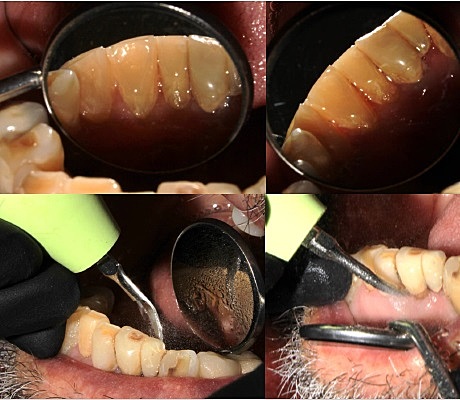

• Modelos de estudio y fotografías intraorales

Modelos de estudio y fotografías intraorales

Al paciente se le tomaron modelos de estudio y fotografías intraorales.

• Segunda cita Profilaxis

Segunda cita Profilaxis

Al paciente se le realizó la fase higiénica para remover la placa dentobacteriana.